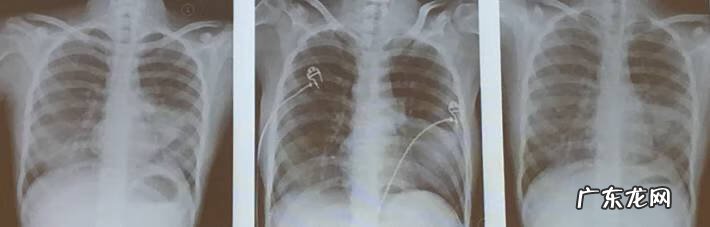

文章插图

出院日、出院1月、出院2月胸片